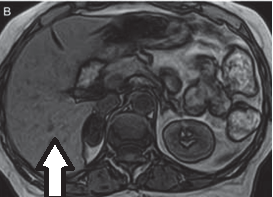

Świadczenie usług medycznych …

Jakie struktury anatomiczne uwidoczniono na obrazie USG?

Ilustracja do pytania 33

A. Pęcherz moczowy z kamieniami.

B. Ciężarna macica z czterema płodami.

C. Nerka lewa ze złogami.

D. Pęcherzyk żółciowy z kamieniami.